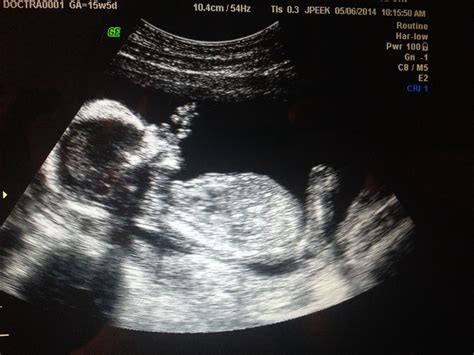

At 9 weeks, the fetus is still very small, but several key features can be observed during the 9 week sono:

• Heartbeat: One of the most exciting moments is hearing and seeing the fetus's heartbeat. At this stage, the heartbeat is usually visible and can be detected with a Doppler device.

• Embryo: The embryo itself is about the size of a grape and has a distinct shape. The head is large in proportion to the body, and the tail is still present.

• Limbs and Organs: The beginnings of the arms, legs, and internal organs are visible, although they are still in the early stages of development.